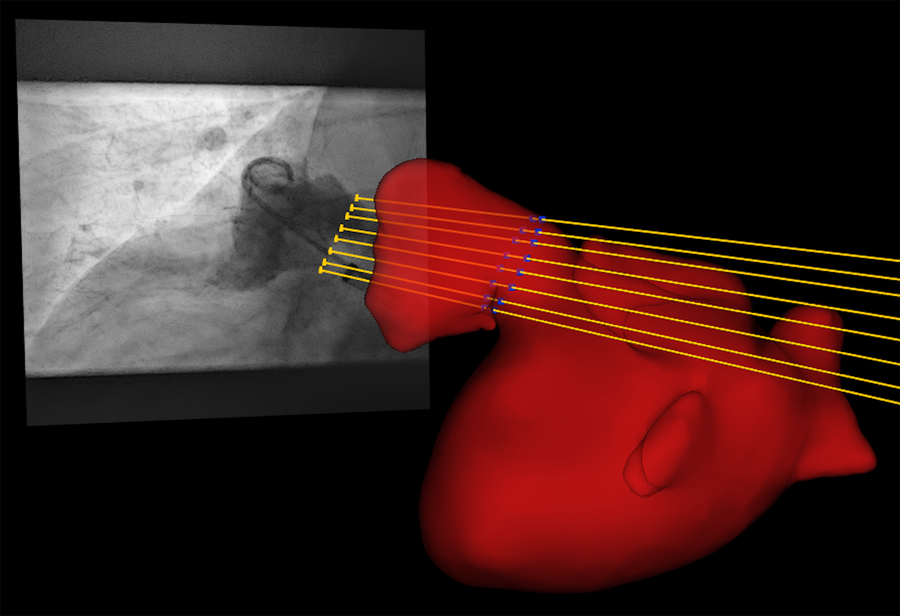

Quantitative comparison of CMR and XR for LAA dimension assessment requires measurement of the respective parameters at the same anatomical location. Since the procedure was performed according to the current clinical recommendations, the respective measurements were done at the location of the landing zone as identified by XR during the LAAc procedure. Accurate identification of the periprocedurally XR-identified landing zone in the CMR data was ensured by registration of the CMR and x-ray data in a common 3D-XR system geometry. According to the geometry values of the XR system stored in a digital imaging and communication in medicine (DICOM) standard image for each XR measurement, each image was visualized geometrically correctly in the 3D XR system geometry. Patient-specific 3D surface meshes were derived from the 3D CMR after manual segmentation of the respective structures using 3DSlicer [www.slicer.org, (34)]. Manual registration of the surface meshes to the XR system geometry was achieved with 3D-XGuide (35). Similar to previous work (36), each XR-derived landing zone was localized in 3D by calculating the intersection points of the projection lines with the 3D surface mesh (Figure 1). A respective 2D CMR image aligned with the landing zone was generated by multi-planar reconstruction (MPR), thus ensuring measurements in the CMR at the same anatomical location as chosen by periprocedural XR.

Figure 1

By intersection of the projection lines (yellow lines) of the landing zone identified in XR (yellow dots) with the left atrial appendage segmented from pre-procedural registered CMR (red), the landing zone was localized in 3D (blue dots).